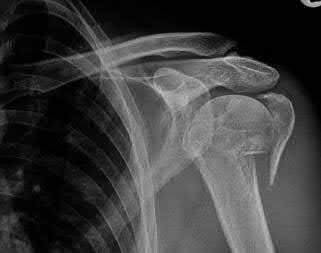

A 22-year-old male falls onto an outstretched hand and sustains a displaced fracture through the proximal pole of the scaphoid. Avascular necrosis of the proximal pole is highly likely due to the disruption of its primary vascular supply. Which vessel provides this critical retrograde perfusion?

Explanation

The primary blood supply to the scaphoid is from the dorsal carpal branch of the radial artery, which enters the dorsal ridge of the scaphoid at the waist and courses proximally. This retrograde blood flow makes proximal pole fractures highly susceptible to avascular necrosis and nonunion. The superficial palmar branch provides a minor supply (about 20%) to the distal pole.